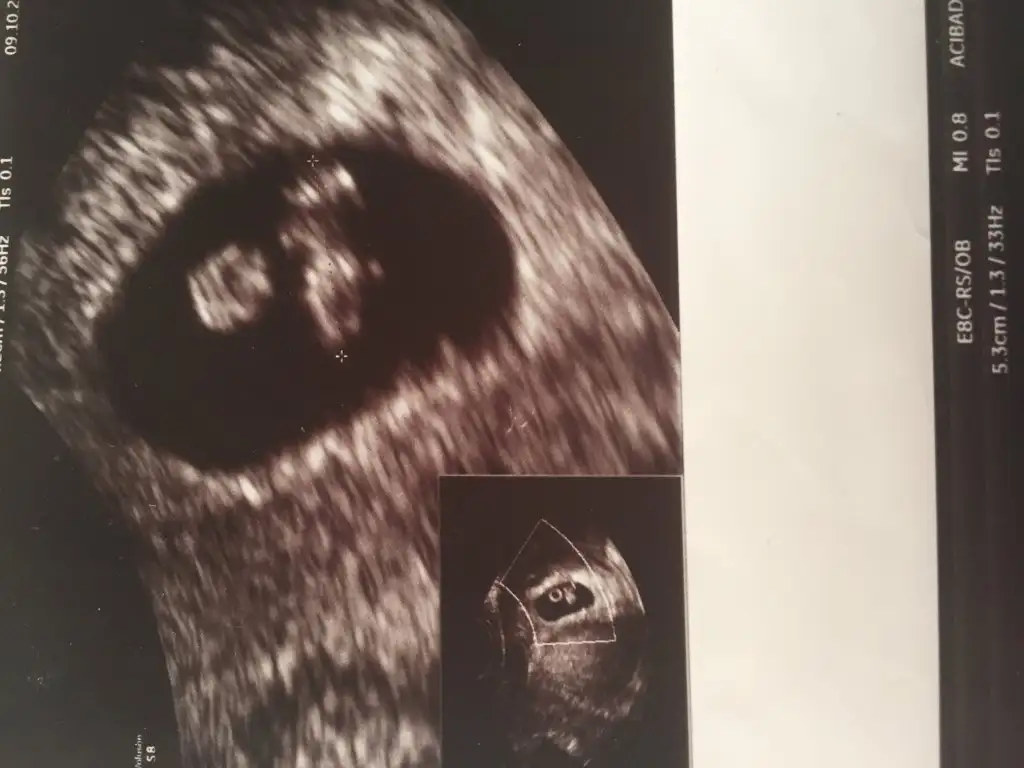

Kizlar sizce benim bebeisimin cinsiyeti nedir burada 7 haftaliktii..

Burda tam 6+6. Bende anlamadim. Karindan ya da vajinal farkli oluyor diye okuyunca sastim kaldim. Ikinci hamileligim. Ilk bebegim erkekti. Ve o sagdaydi. O yuzden isin icinden cikamadim. Ikiside farkli olunca acaba cinsiyeti farkli mi diye dusundum. Baska yardimci olabilecek arkadaslar varsa cvp bekliyorum

Arkadaslar 7 haftalık usg resmim bebis 8 mm oldugu icin daha net